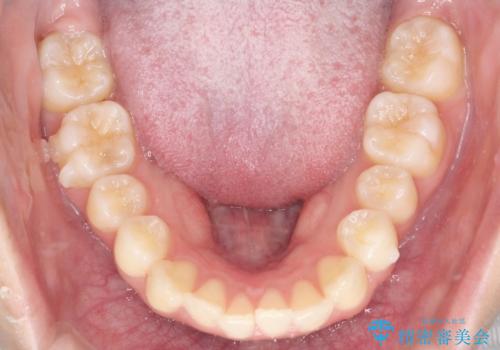

初診時の歯並びの状態としては、上下ともに全体に及ぶの中等度のがたつき(叢生)があり、全特に左上の前歯は1本だけ引っ込んでいる状態でした。

抜歯は行わず上顎の奥のスペースを利用して歯をスライドする方法の他に歯列弓の拡大やディスキング(歯と歯の間の隙間を作る処置)を行い叢生を改善しました。

歯の大きさの不揃いが原因の正中のズレは、ディスキング量を調整することで合わせています。

上の歯を後ろに送る方法として、歯茎に入れた小さなネジからゴムかけをして歯列全体を後ろに引っ張りました。

見た目、嚙み合わせ及び、治療期間や施術内容に大変ご満足いただきました。